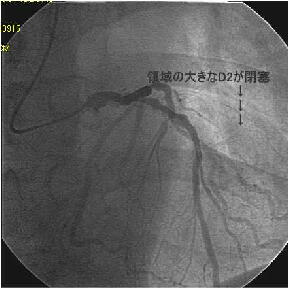

�܂�pre CAG.

|

|

|